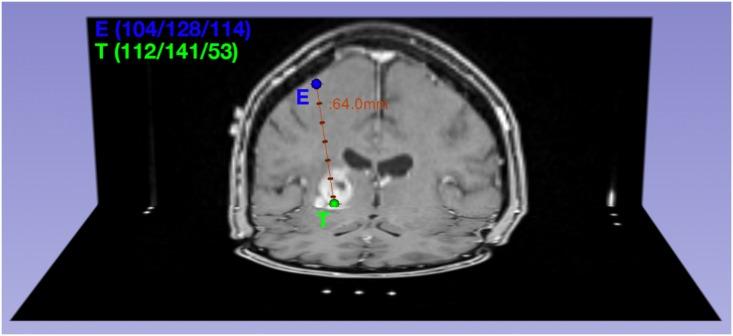

Thirty-seven patients with newly diagnosed glioblastomas were enrolled in this study. ADC maps were acquired preoperatively at 3T and coregistered to the intraoperative MRI that contained the coordinates of the biopsy trajectory. 561 biopsy specimens were obtained; corresponding cellularity was calculated by semi-automatic nuclei counting and correlated to the respective preoperative ADC values along the stereotactic biopsy trajectory which included areas of T1-contrast-enhancement and necrosis.